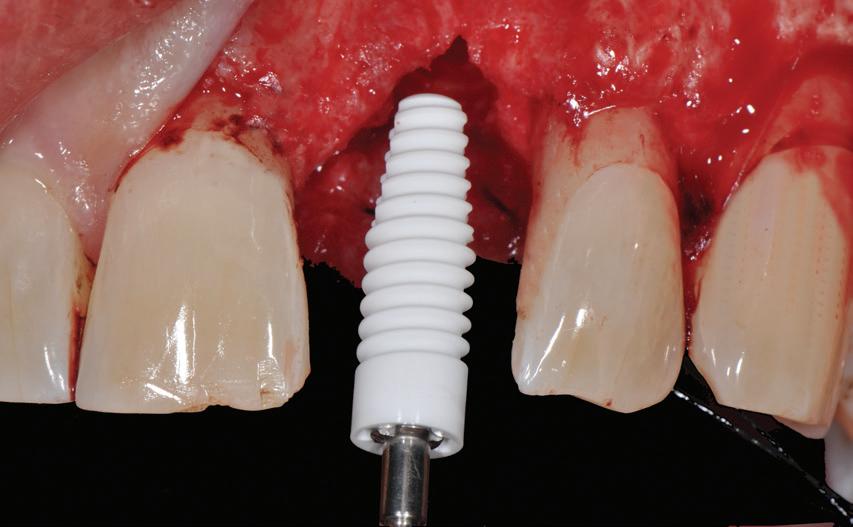

Regretatul Profesor Sami Sandhaus, originar din Cernăuți și un prieten constant al scenelor românești, aducea în atenția stomatologiei mondiale în urmă cu peste 50 ani implanturile non-metalice, dintr-un oxid de alumină, insuficient de stabil pe atunci. La începutul anilor 2000, începea să „strălucească” dioxidul de zirconiu ca material pentru implanturile dentare. „Materialul natural de pornire, zirconiul, este într-adevăr un metal; totuși, prin reacția cu oxigenul, este complet oxidat în dioxid de zirconiu și, astfel, transformat ireversibil într-o ceramică.”

O recenzie excelentă a materialelor și caracteristicilor implanturilor ceramice constituie subiectul articolului de Educație Continuă. Sunt detaliate, de asemenea, conceptele de restaurare a implanturilor ceramicemonobloc sau bicomponent, împreună cu avantajele în ceea ce privește flexibilitatea protetică și indicațiile clinice. În plus, sunt comparate estetica pe suportul din titan față de cel ceramic, riscul de periimplantită, ratele de osteointegrare, succes și de supraviețuire. Concluzia auto-

rilor este categorică: implanturile ceramice moderne, corect indicate și manipulate își croiesc drum sigur către cabinetele de implantologie convenționale, alături de titanii din titan.

mulți ani. Cu toate acestea, odată cu introducerea dioxidului de zirconiu la începutul anilor 2000 ca material de implant dentar de încredere și cu dezvoltarea continuă a suprafețelor implantare microasperizate, acest lucru a început să se schimbe.

Astăzi, implanturile ceramice își pierd din ce în ce mai mult reputația ca produs de nișă și își găsesc progresiv drumul în cabinetele de implantologie „convenționale”. Acest fapt se datorează parțial sporirii gradului de conștientizare a sănătății în rândul populației și cererii crescute pentru restaurări non-metalice. În plus, dezvoltarea ulterioară a materialelor, suprafețelor și conceptelor de aplicare și, prin urmare, fiabilitatea crescută, este, fără îndoială, un motiv major pentru acceptarea crescută a implanturilor ceramice de către stomatologii care practică implantologia.